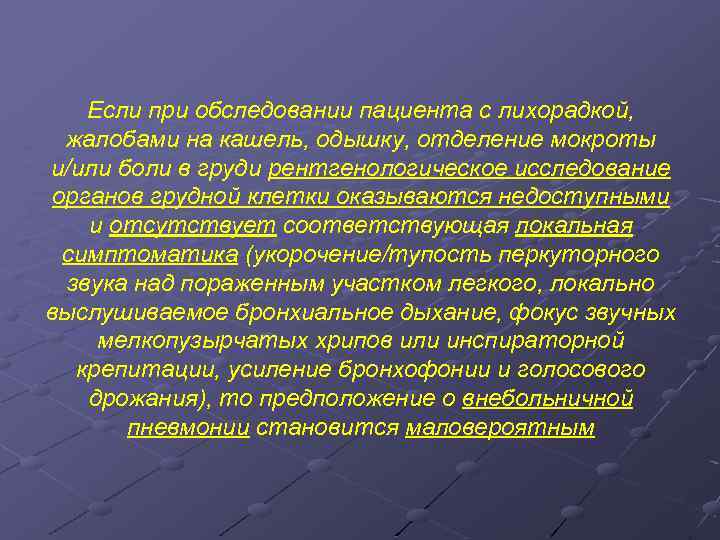

Острая внебольничная пневмония по МКБ-10: признаки и примеры